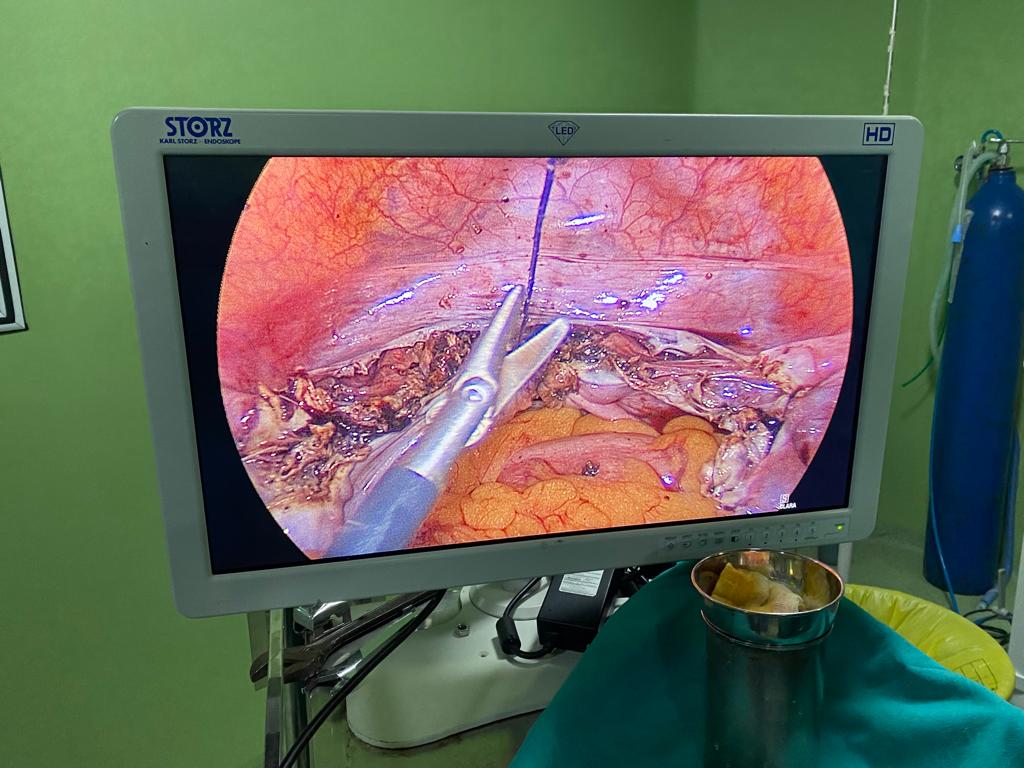

Acute Cholecystis, Mucocele Gallbladder with big stone at the neck. Completely done Laparoscopically